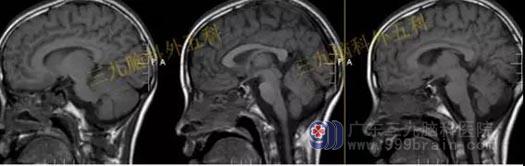

头部MR检查:鞍区示一类圆形长T1稍长T2异常信号影,FLAIR序列呈等信号,边界清晰,边缘光整,范围约为1.6×1.8×2.2cm,增强扫描呈明显均匀强化。视交叉受压稍上抬,双侧颈内动脉局部与病灶关系密切。

手术过程:内镜下经鼻蝶垂体腺瘤切除术,垂体位于左侧,质地硬,沿着肿瘤包膜全切肿瘤

头部MR提示原病灶已切除。